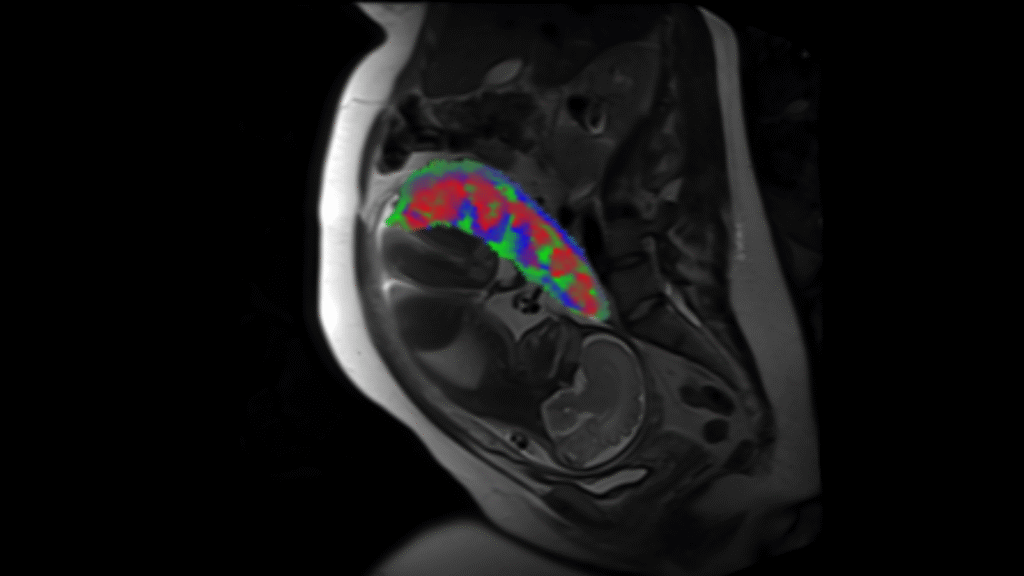

Placental Perfusion and Outcomes

Perfusion Measures in Pregnancy Associated with Nutrition & Fetal Outcomes

Maternal obesity, dietary intake, and nutrition status during pregnancy have been linked with preeclampsia, gestational hypertension, maternal cardiovascular biomarkers during pregnancy (insulin, insulin resistance and triglycerides), and child birth outcomes in epidemiologic research. The placenta is likely enmeshed in the causal pathways, but we have limited understanding of how these exposuresimpact placentation and placental function. Abnormal placentation and associated consequences are theorized to impact the pathophysiology of preeclampsia and other adverse outcomes, and nutritional status and dietary intake may be a key potentially modifiable factor in these associations.

We are assessing perfusion measures in the placenta associated with nutrition and fetal outcomes. Specifically, we are looking at microcirculation within different layers of the placenta to evaluate early markers of maternal or fetal health.

This work is in collaboration with Dr. Beth Widen